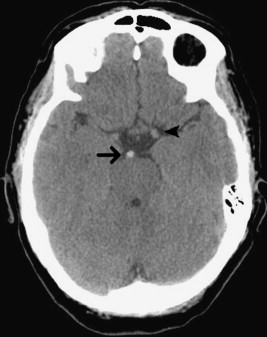

Figure 2 – A Basilar Artery Thrombus shown on Plain CT Head:27

- Middle Cerebral Artery (MCA) Thrombus24

- Basilar Artery Thrombus25